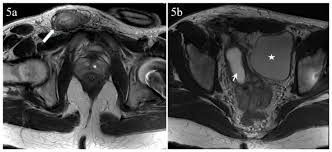

Hasil radiologi seseorang dengan PMDS (europepmc.org)

Hasil pemeriksaan lanjutan yang dilakukan Rob menunjukkan bahwa ia mengalami Persistent Mullerian Duct Syndrome (PMDS), alias sindrom saluran Mullerian persisten.